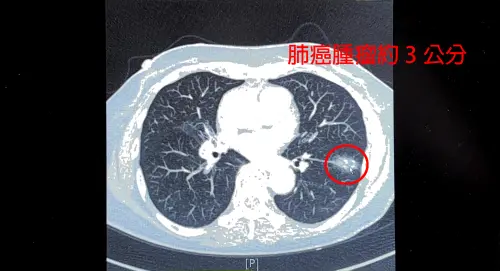

女不菸不酒染肺結核!肺癌風險「竟飆高200倍」 醫揭高風險族群

一名75歲女性從不抽菸、喝酒,日前健檢接受低劑量電腦斷層(LDCT)檢查,意外發現左下肺葉有接近3公分的惡性腫瘤,而因10多年前曾罹患肺結核,導致肺部留下堅硬...